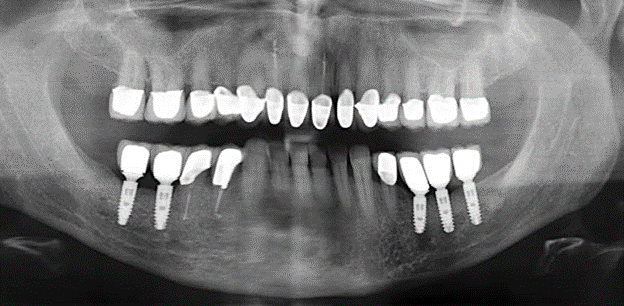

Eine 52-jährige Patientin stellte sich nach Zahnverlust im 3. Quadranten erstmals 2004 vor. Sie hatte den Wunsch nach einer prothetischen Neuversorgung. Im Rahmen der parodontologischen und radiologischen Diagnostik zeigte sich ein ausgeprägter parodontologischer Behandlungsbedarf. Die Zähne 48, 28, 27 zeigten zudem eine infauste Prognose und wurden entfernt (Abb. 1). Nach der erfolgreich abgeschlossenen systematischen PARTherapie wurde eine festsitzende implantatprothetische Versorgung mit Insertion von fünf Implantaten in Regio 35, 36, 37 und 46, 47 durchgeführt. Die prothetische Versorgung der natürlichen Zähne erfolgte mit verblendeten Zirkonoxidkeramikkronen, die Implantate wurden mit zweiteiligen individuellen Zirkonoxidabutments und ebenfalls verblendeten Kronen aus einer Zirkonoxidkeramik versorgt (Cercon base colored, Dentsply Sirona Lab). Die definitive Insertion der prothetischen Versorgung erfolgte im Jahr 2005.

Im Rahmen der ZehnJahresKontrolle zeigten sich keine Hinweise auf einen fortschreitenden parodontalen Attachmentverlust oder einen periimplantären Knochenverlust (Abb. 3).